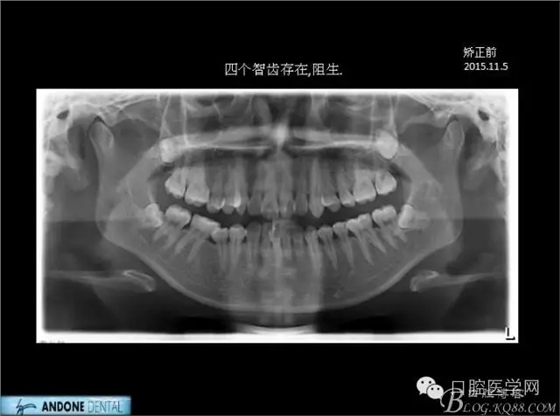

直面型下中度擁擠的不拔牙矯治